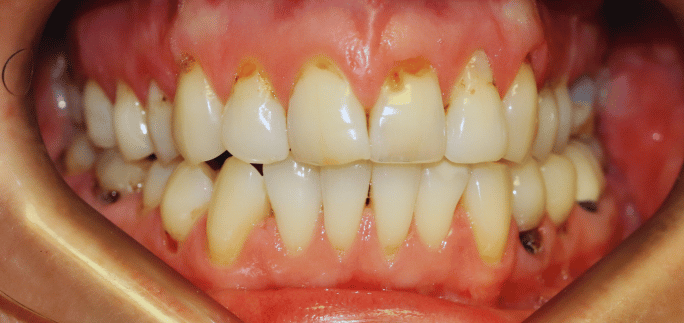

Before

Before